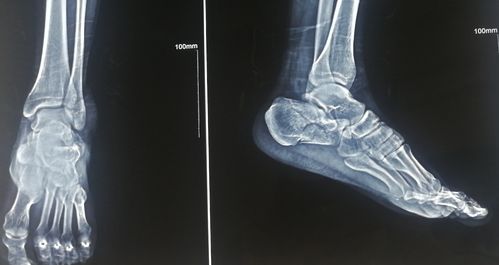

正常跟骨片子图片,骨折片子图

跟骨骨折大l切口内固定

求助:大神看片子_骨折康复_医疗健康_医疗健康其他